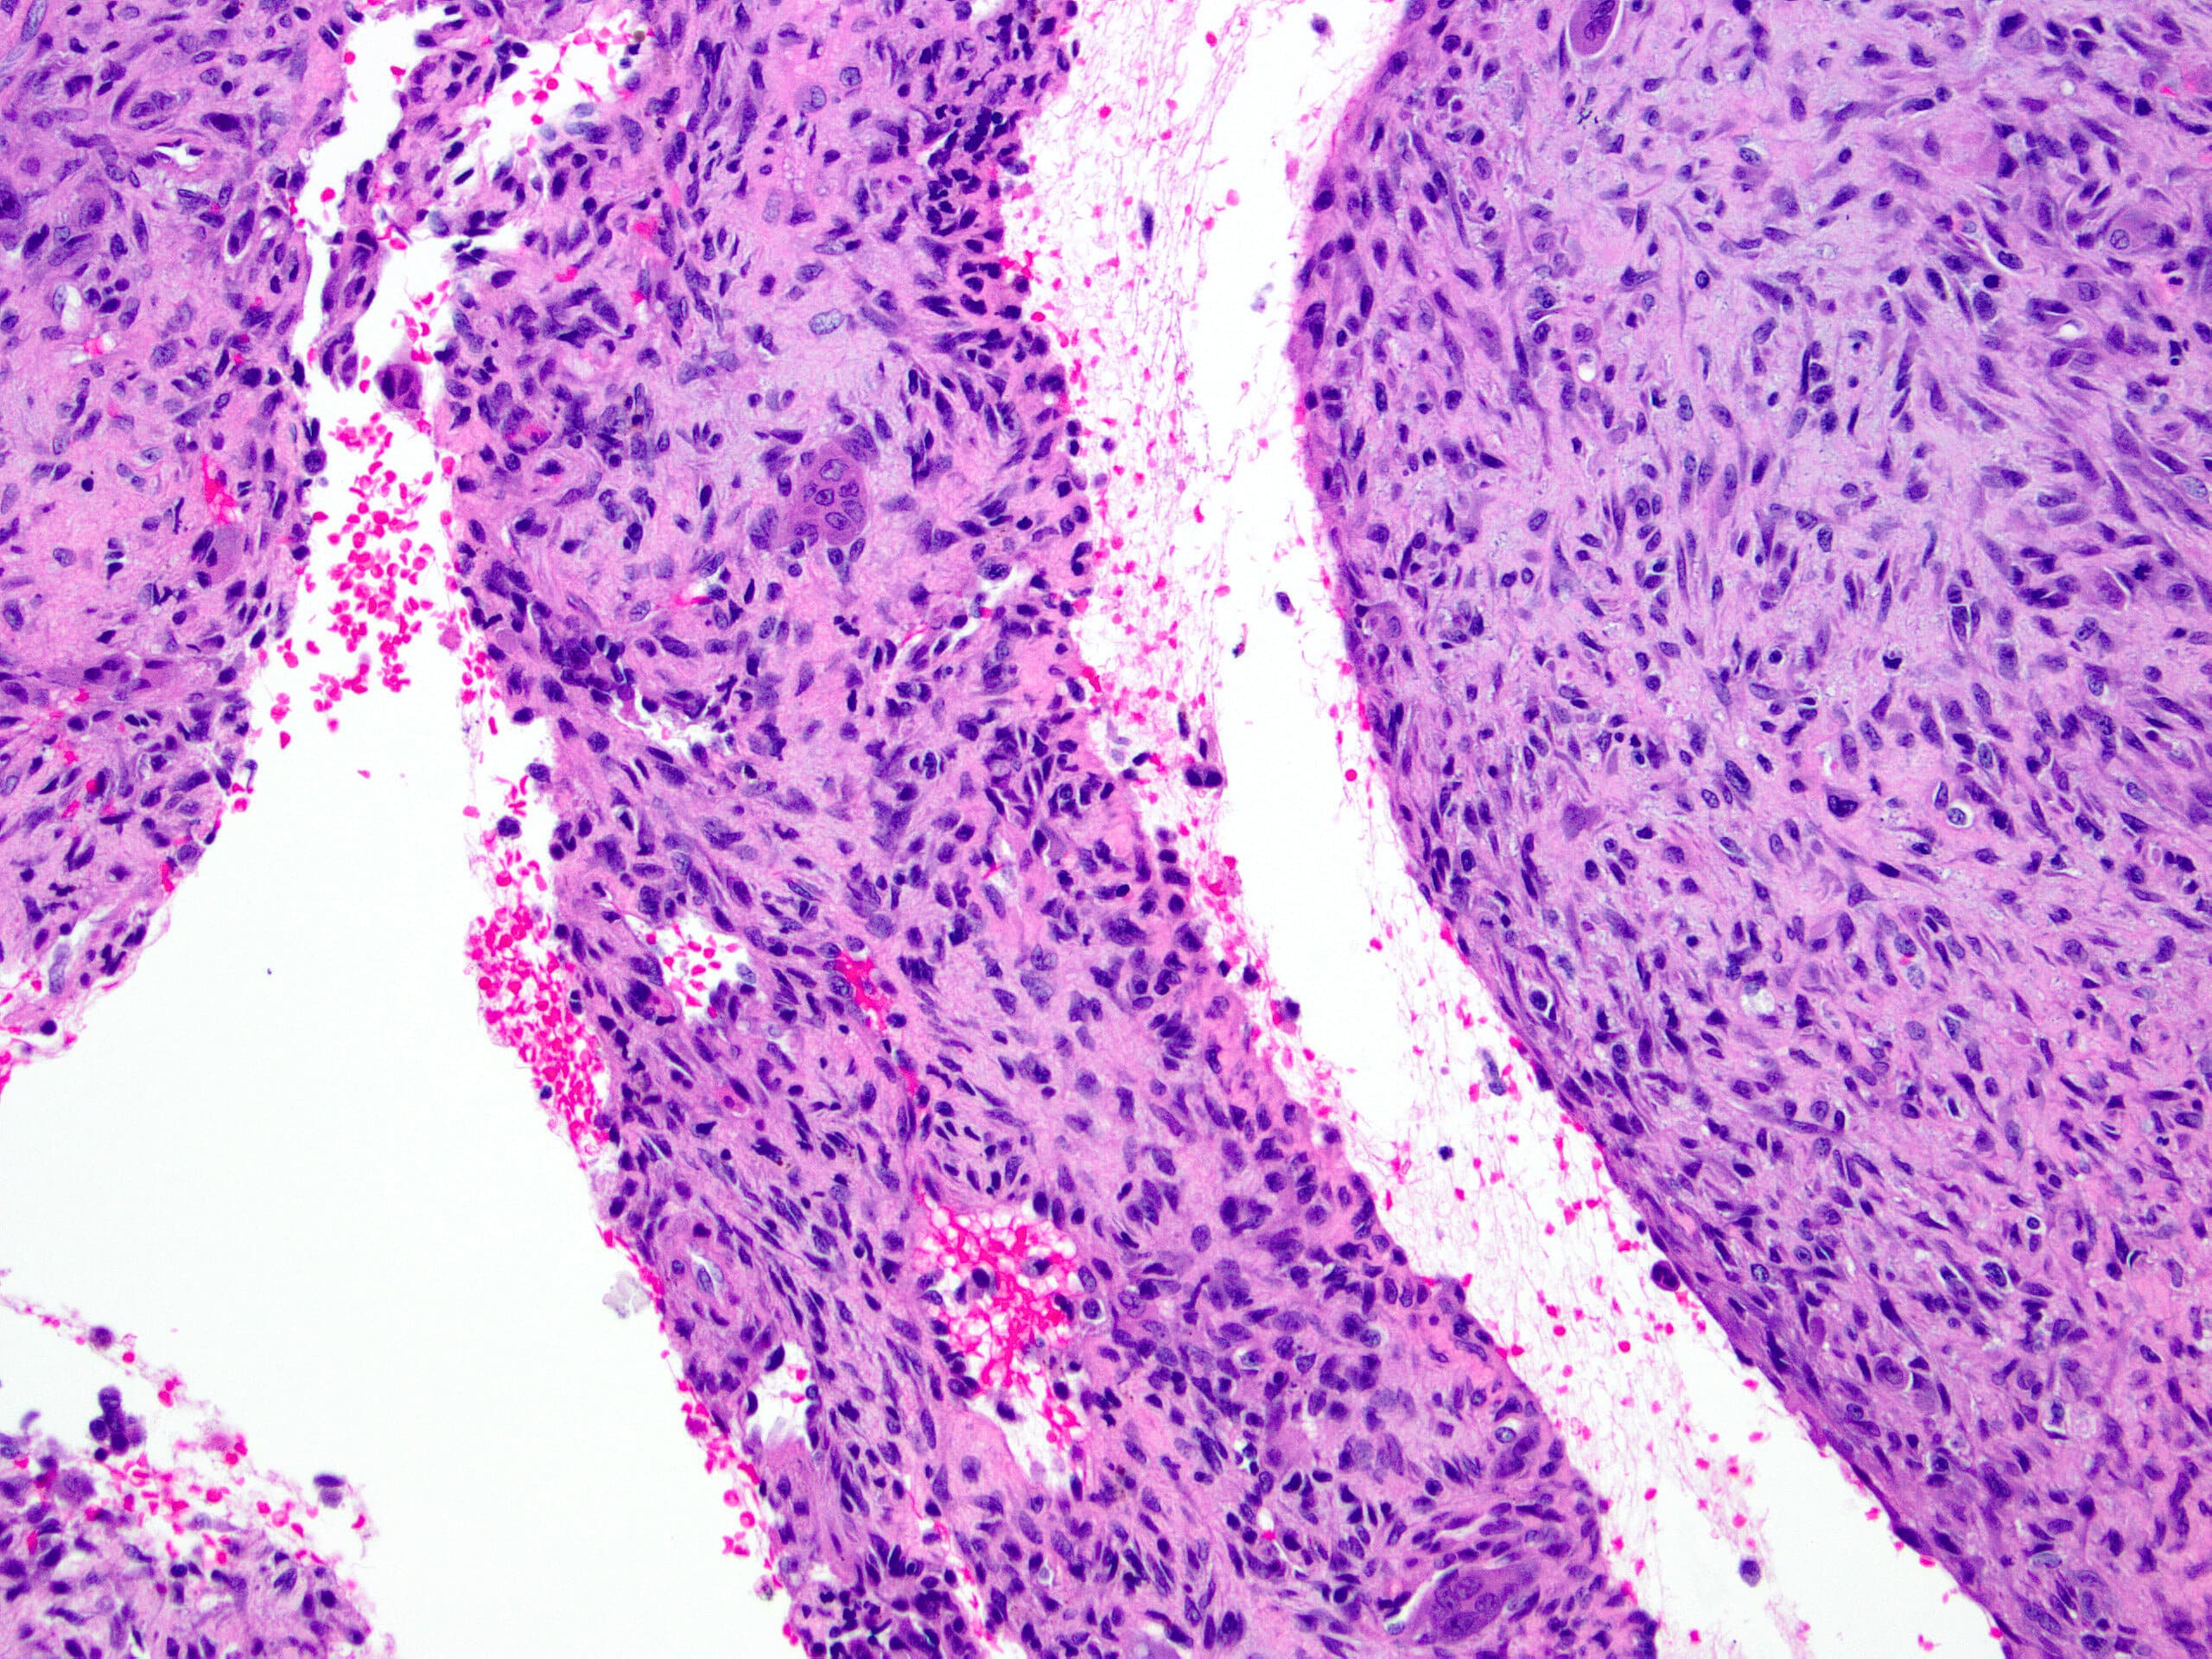

- Multiloculated cystic lesion

- Blood filled cystic spaces separated by cellular septa containing fibroblasts, giant cells and woven bone

- Calcified, basophilic material (blue reticulated chondroid-like material)

- Necrosis not common but mitotic activity is easily identified

- No cytologic atypia (Am J Clin Pathol 2015;143:823)

- Numerous giant cells in connective tissue that line large sinusoidal spaces

Microscopic (histologic) images

Contributed by Elham Nasri, M.D. and Kelly Magliocca, D.D.S., M.P.H.

A. Aneurysmal bone cyst. The H&E shows cystic spaces with stromal giant cells. Rearrangement of USP6 gene confirms the diagnosis in the above clinical and radiographic context.